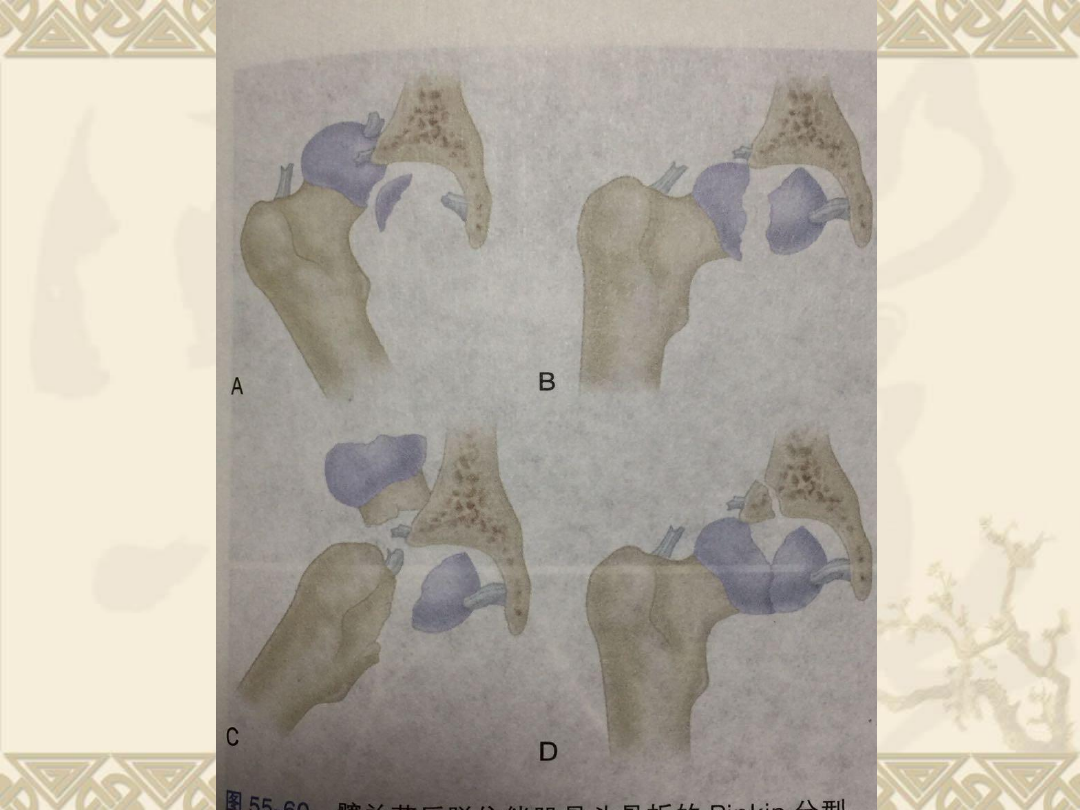

回顾股骨头骨折分型

v

Ⅰ型

:髋关节后脱位伴股骨头中央凹头端骨

Ⅱ型:

髋关节后脱位伴股骨头中央凹尾端骨

Ⅲ型:

上述Ⅰ型

或Ⅱ型

后脱位同时伴股骨

颈骨折

Ⅳ型

上述Ⅰ型、Ⅱ型或

Ⅲ型

后脱位同时

伴髋臼骨折